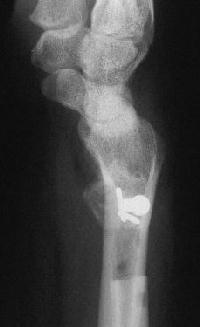

Case 1. Typical Xray findings of congenital Madelungs.